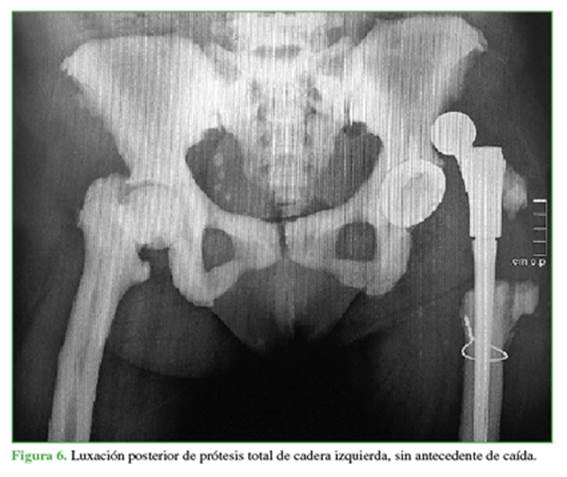

En marzo de 2018, sin antecedente de caída, la paciente consulta por el servicio de urgencias de la institución por dolor intenso en cadera izquierda, acortamiento de la extremidad y limitación para el apoyo y la marcha. La radiografía de control evidencia luxación posterior de prótesis total de cadera izquierda (Figura 6). Tras varios intentos de reducción cerrada de la luxación bajo anestesia general y persistencia de inestabilidad, se realiza reducción abierta de luxación de prótesis, con hallazgo intraoperatorio de desinserción de mecanismo abductor de la cadera, sin signos de infección o aflojamiento de los componentes, por lo que se realiza reparación y nueva fijación a aleta de metáfisis de vástago femoral, sin complicaciones (Figura 7).